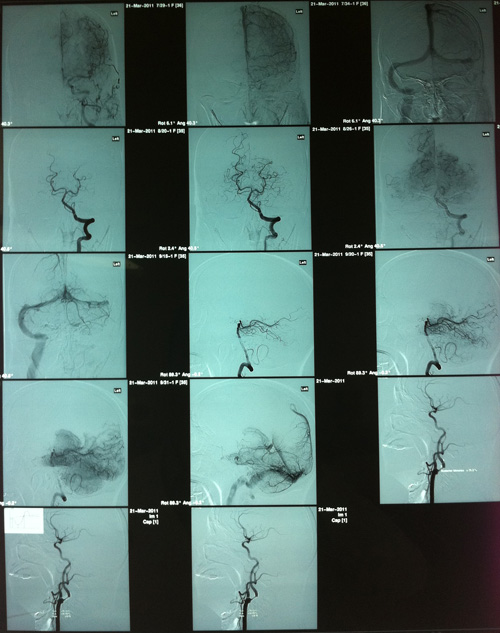

DSA(2011-3-21,人民医院):双侧颈内动脉起始部及右颈内动脉虹吸段及右侧大脑后、小脑上动脉起始段多发动脉硬化斑块形成,伴不同程度的管腔狭窄。

该患者左侧颈内动脉环周低回声斑,管腔狭窄约75%-80%,症状明显,且有高血压及糖尿病史,符合颈动脉内膜剥脱术手术指征。于2011年3月25日,由协作组张勤奕教授顺利为其实施了左侧颈动脉内膜剥脱术。